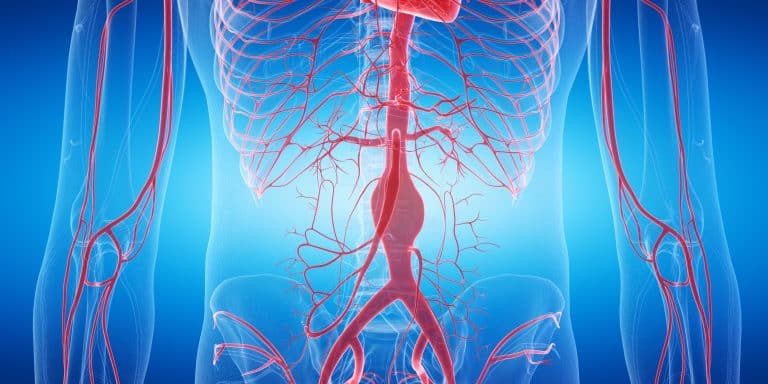

Što je bypass

U razvijenim zemljama glavni uzrok smrti su kardiovaskularne bolesti. Životni stil koji danas vodimo često vodi problema s krvnim žilama, a i sa srcem. Naše žile i naše srce čini naš kardiovaskularni